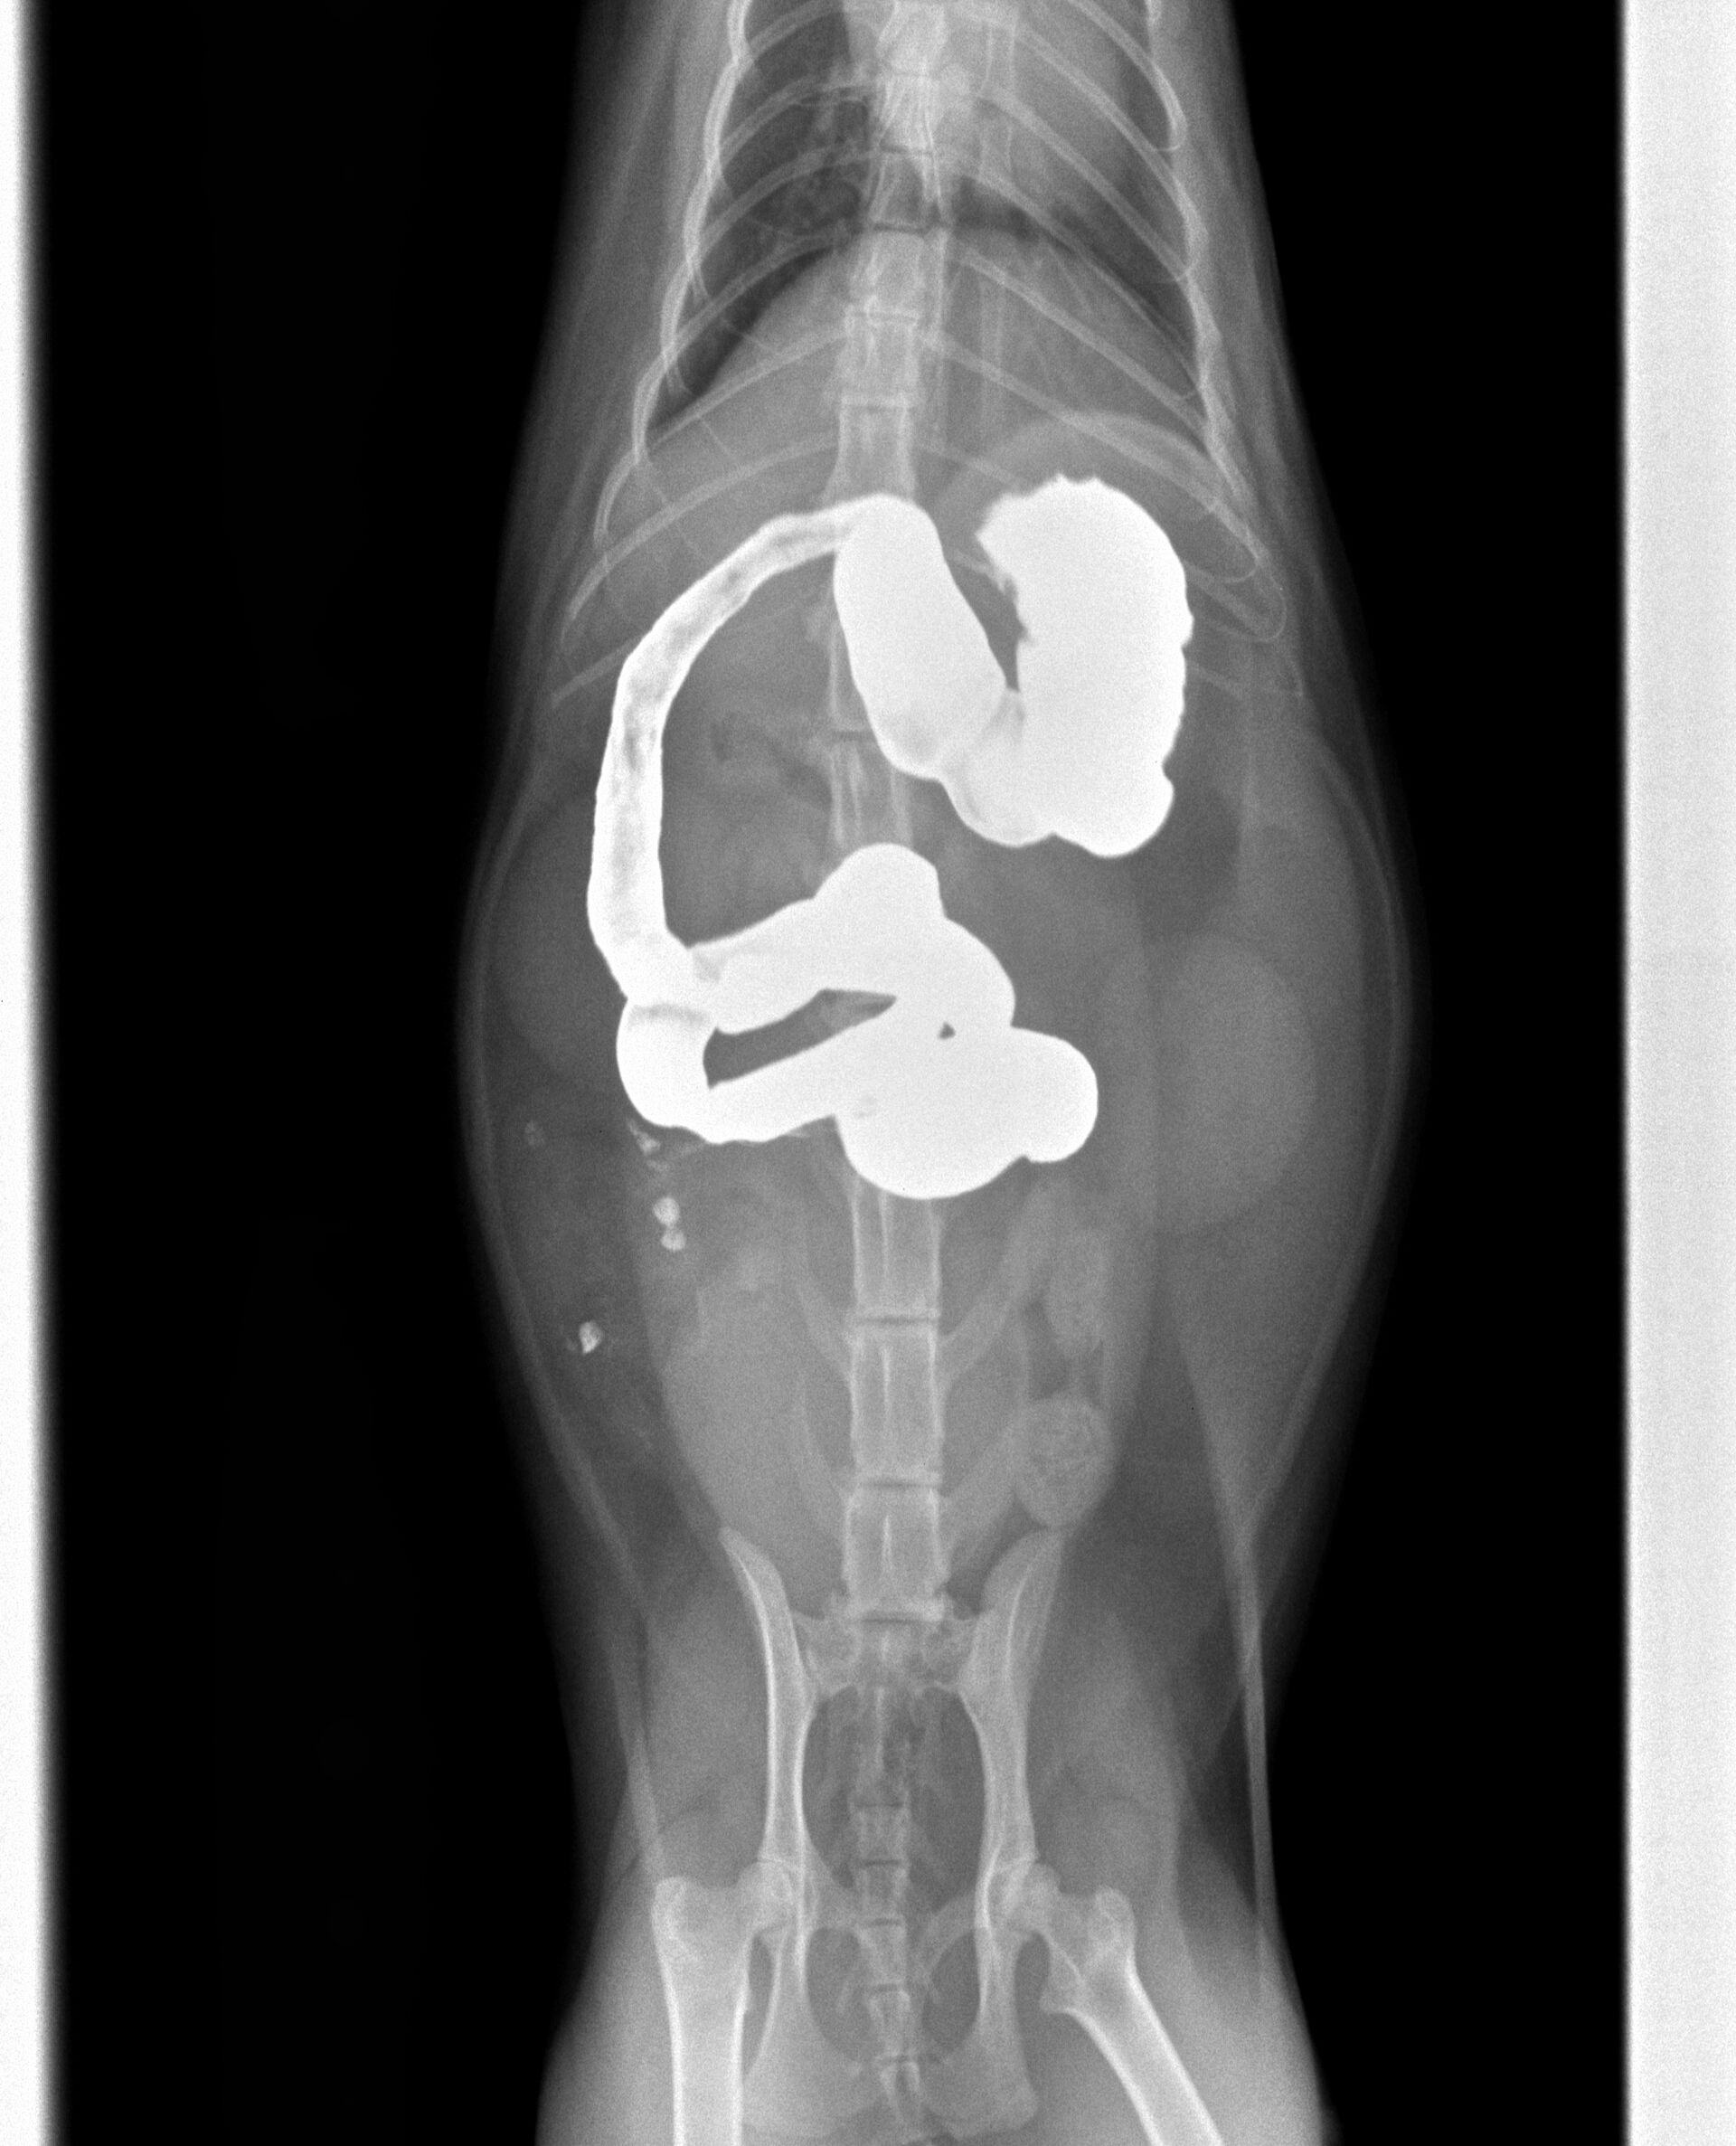

ところが、翌日また来院され、状態は全く変わらず、相変わらず食欲がなく、茶色のものを吐くようになったということでした。このことから腸閉塞を疑い、バリウム検査を行いました。バリウムを飲ませてから4時間目のレントゲンが下の写真ですが、小腸のある場所(黄色矢印)でバリウムが止まってしまい、それ以降は流れていません。胃内はバリウムで満たされています。通常は2-3時間で胃の中のバリウムはほとんどが流れ出てしまいます。